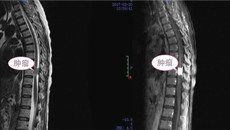

冼某是广西女子监狱服刑人员,因“双下肢乏力3个月、加重并截瘫、大小便失禁1周”于2017年3月20日由广西监狱总医院转入一附院外六科。 患者于3个月前开始出现双下肢麻木、活动乏力,1周以来呈进行性加重, 并迅速发展至截瘫,大小便失禁。据了解,患者3个月前始已出现身体不适,但未及时汇报,自以为“练功”可以解决问题,而致病情拖延,监狱干警和管理人员及时发现了她的病情,并将她转送广西监狱总医院...04.112017